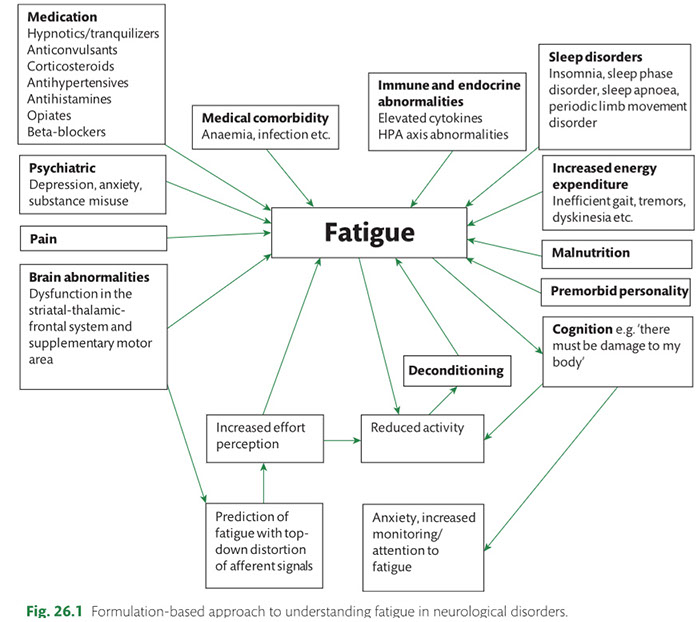

Many observations suggest that CFS could derive from residual damage to the reticular activating system (RAS) of the upper brain stem and/or to its cortical projections. It should be pointed out that although the larger right greater than left asymmetry in regional cerebral blood flow is found at the parietotempotal level in CFS patients as compared to healthy controls, no significant correlations are found between frontal tracer uptake and right-left parietotemporal asymmetry, on the one hand, and clinically relevant CFS dimensions on the other. Damage to the RAS could be produced by a previous viral infection, leaving functional defects unaccompanied by any gross histological changes.

In this respect, fluorine-deoxyglucose positron emission tomography showed specific metabolism abnormalities in CFS patients (hypometabolism in right mediofrontal cortex and brainstem) as compared with both healthy controls and depressed patients. The most relevant abnormality is brain stem hypometabolism, which has been also reported in single-photon emission computed tomography studies and seems to be a marker for the in vivo diagnosis of CFS